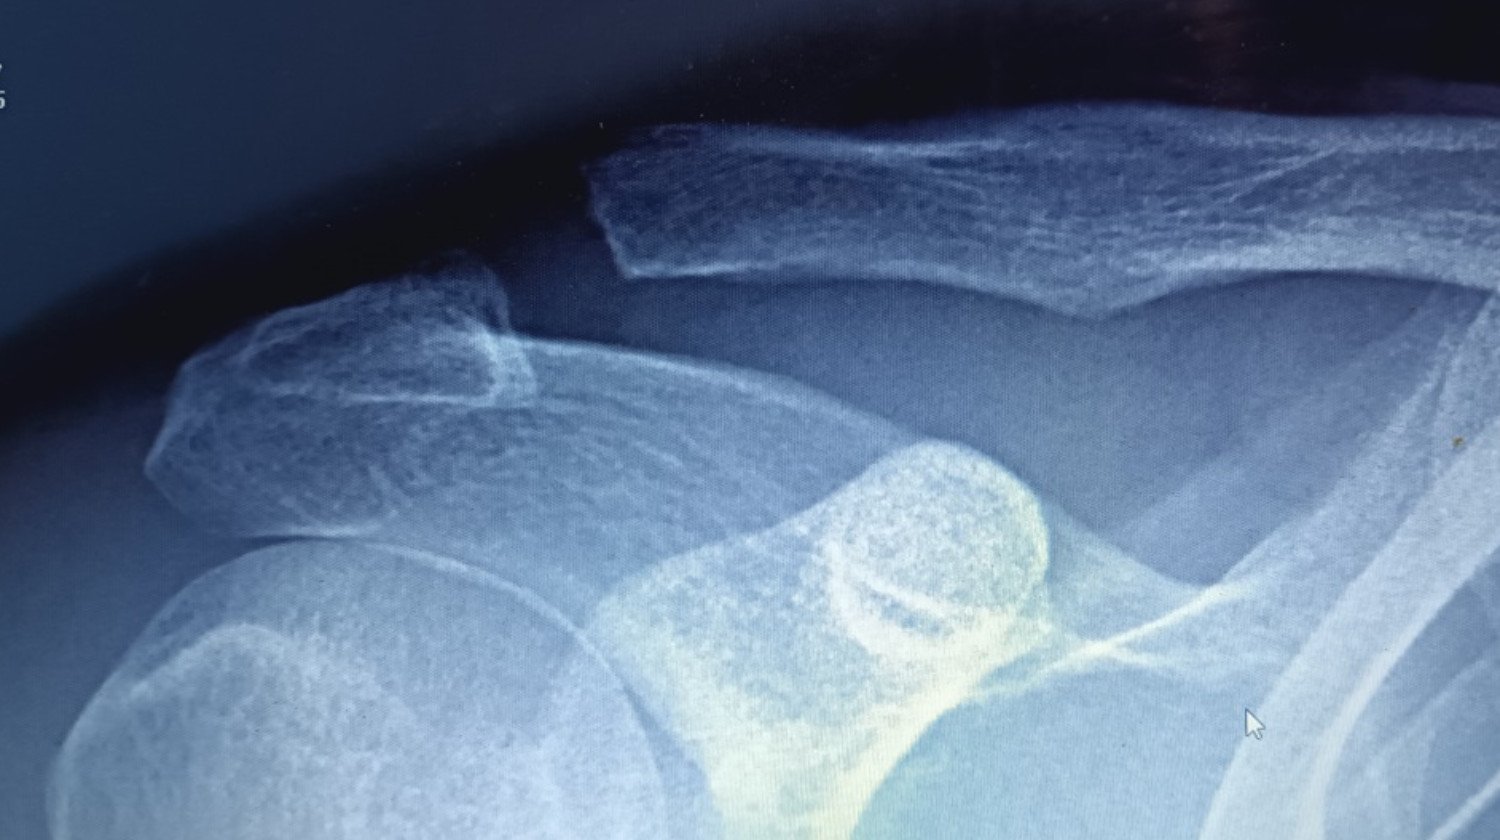

W styczniu przewróciłem się podczas na łyżwach. W wyniku upadku wybiłem bark i złamałem trzon obojczyka. Na początku lekarze nie zauważyli złamania trzonu obojczyka. W dniu upadku zrobiono dwa zdjęcia RTG i kazano chodzić w temblaku. Po 10 dniach na kontroli orzeczono, żeby jeszcze 3 tygodnie niczego nie zmieniać. Po miesiącu, powiedziano, że jeśli nie poprawi się w ciągu 5 tygodni to żeby wrócić. W międzyczasie poszedłem do innego lekarza, który wykrył po zrobieniu RTG złamanie trzonu obojczyka. Do tego czasu wytworzył się tzw objaw "klawisza", gdzie końcówka obojczyka wystaje wyraźnie (można go wcisnąć, ale po zniknięciu ucisku obojczyk znowu wystaje). Po zabiegach magnetoterapii, laseroterapii, naświetlaniu lampą sollux i przyjmowania Osteogenu (na pobudzanie zrostu kości) wyrok jest jeden: Rekonstrukcja więzadeł w zwichnięciu stawu barkowo-obojczykowego.